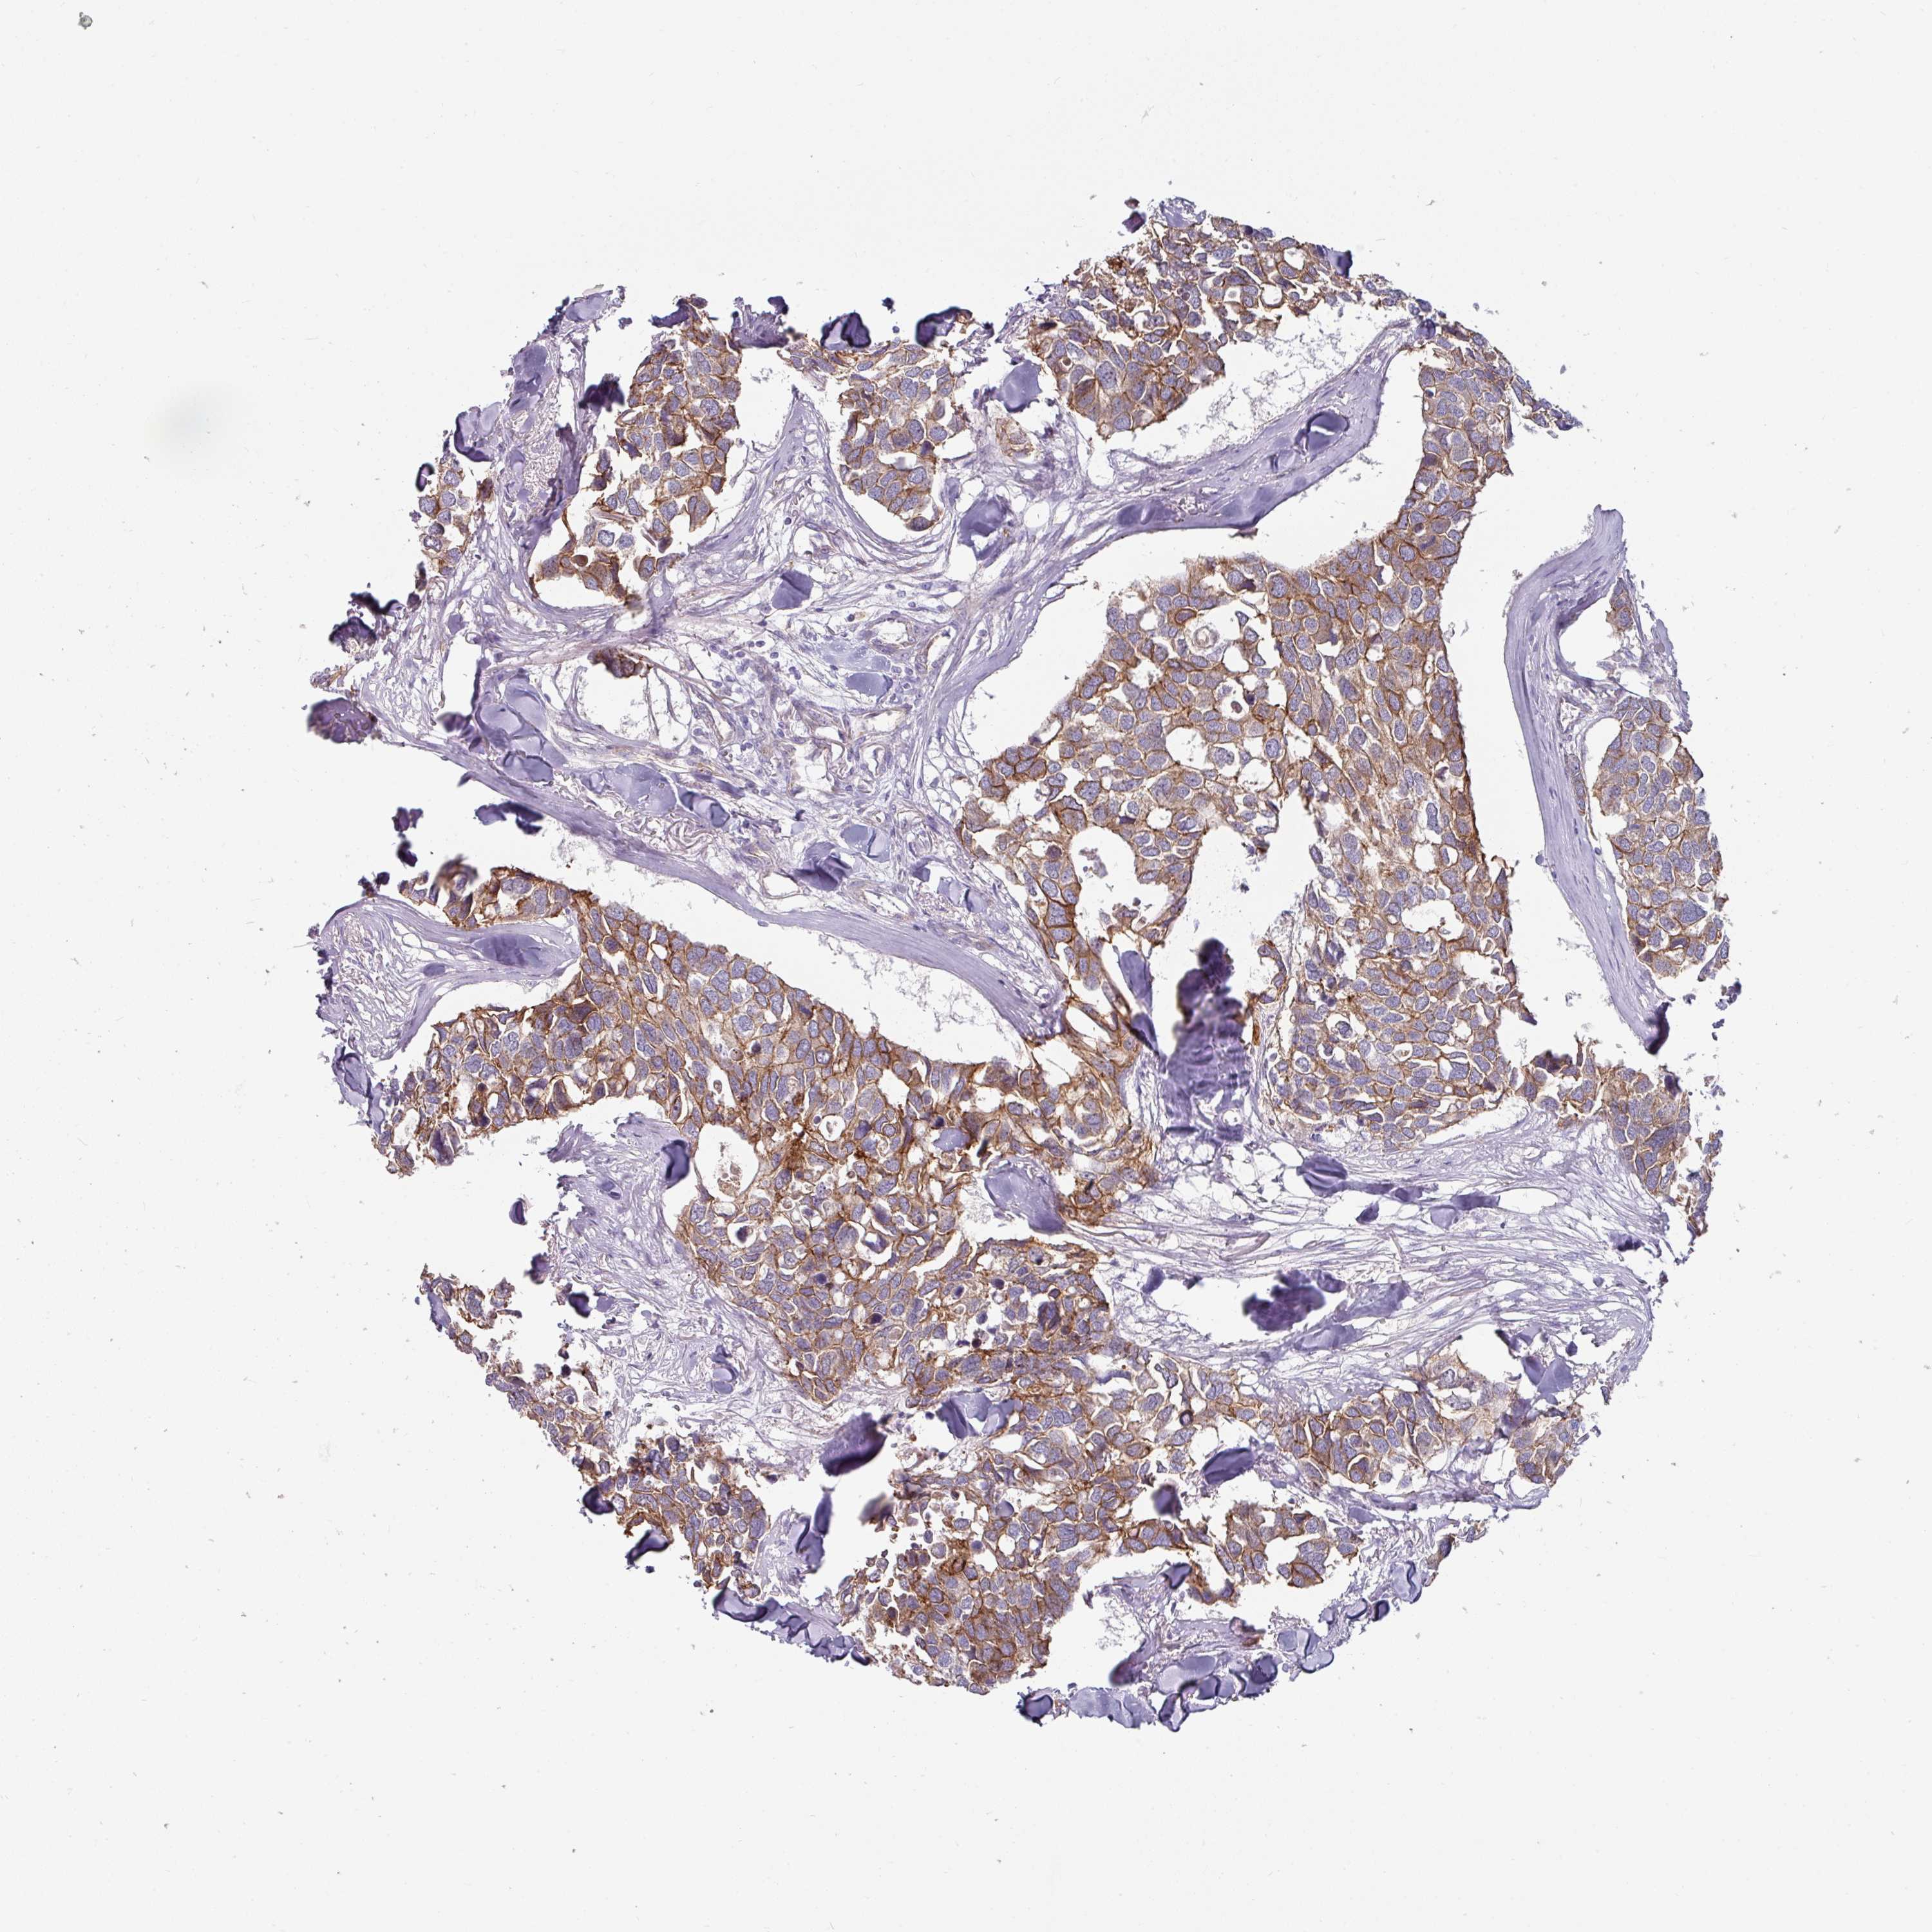

BRCA TCGA BRCA VALIDATION PROTEIN EXPRESSION

ANTIBODIES

AND

VALIDATION